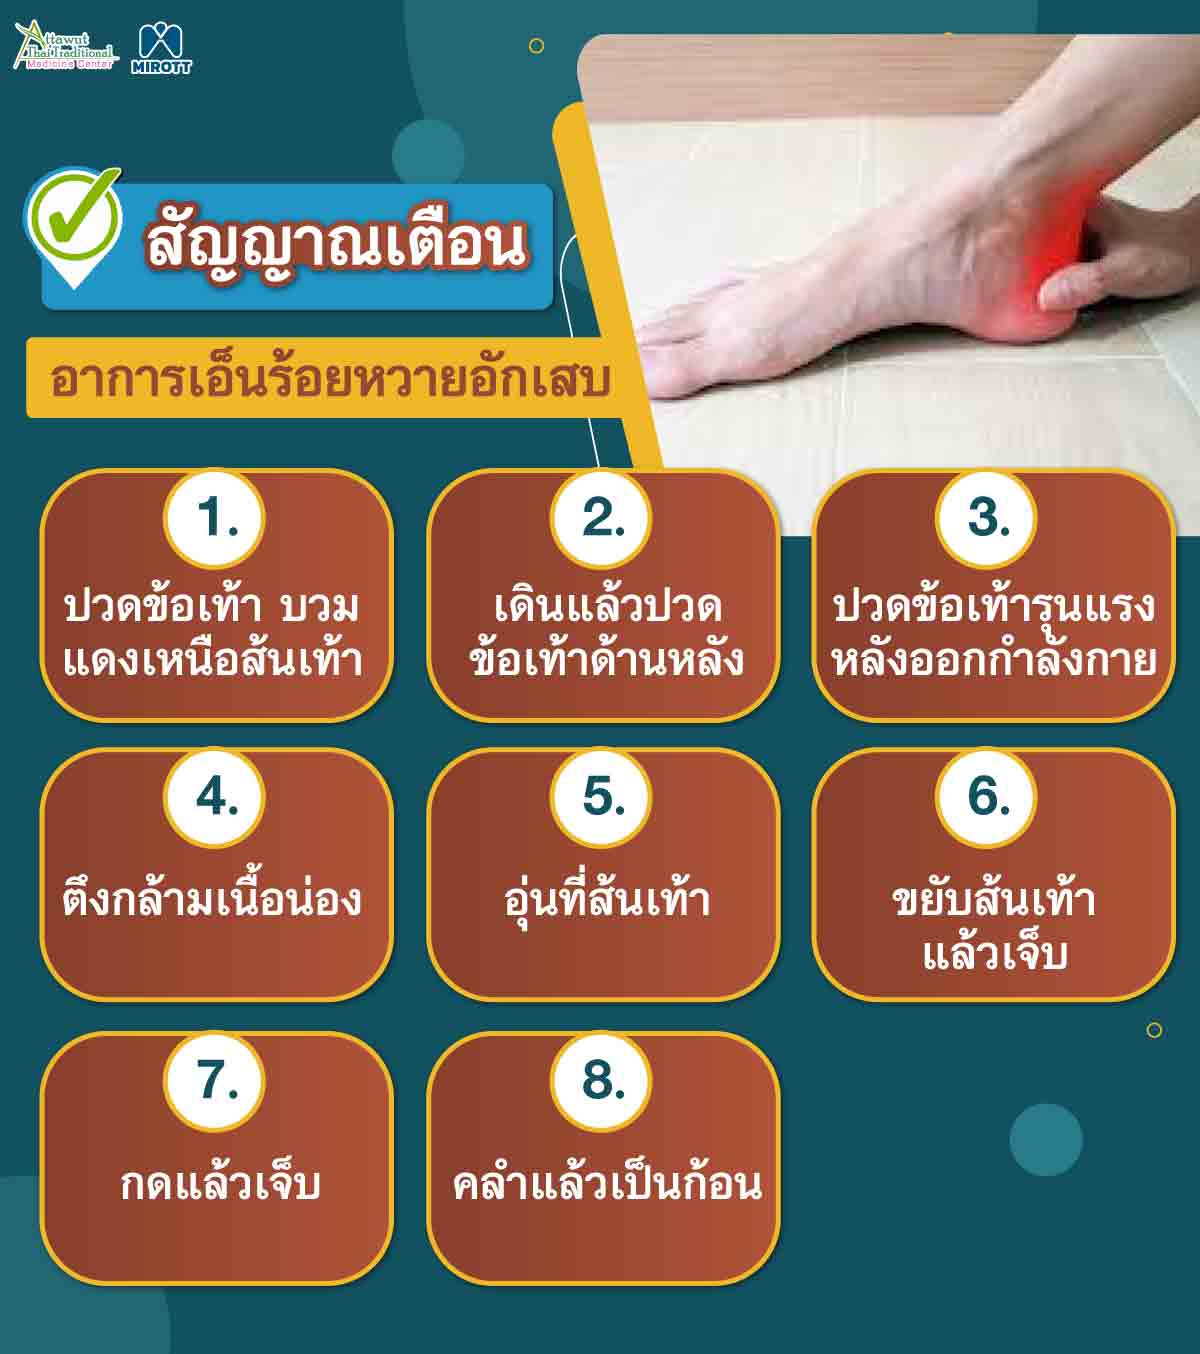

ท่าบริหารเอ็นร้อยหวาย แก้เอ็นร้อยหวายตึง เอ็นร้อยหวายอักเสบ เอ็นร้อยหวายบวม เช็คด่วน! สัญญาณเตือนเอ็นร้อยหวายอักเสบ ที่คนรักออกกำลังกายต้องรู้

เช็คด่วน! สัญญาณเตือนเอ็นร้อยหวายอักเสบ ที่คนรักออกกำลังกายต้องรู้ รักษาเอ็นร้อยหวายอักเสบ ที่ต้นเหตุ ปลอดภัย

เช็คด่วน! สัญญาณเตือนเอ็นร้อยหวายอักเสบ ที่คนรักออกกำลังกายต้องรู้ เอ็นร้อยหวายฉีกขาด – jia1669